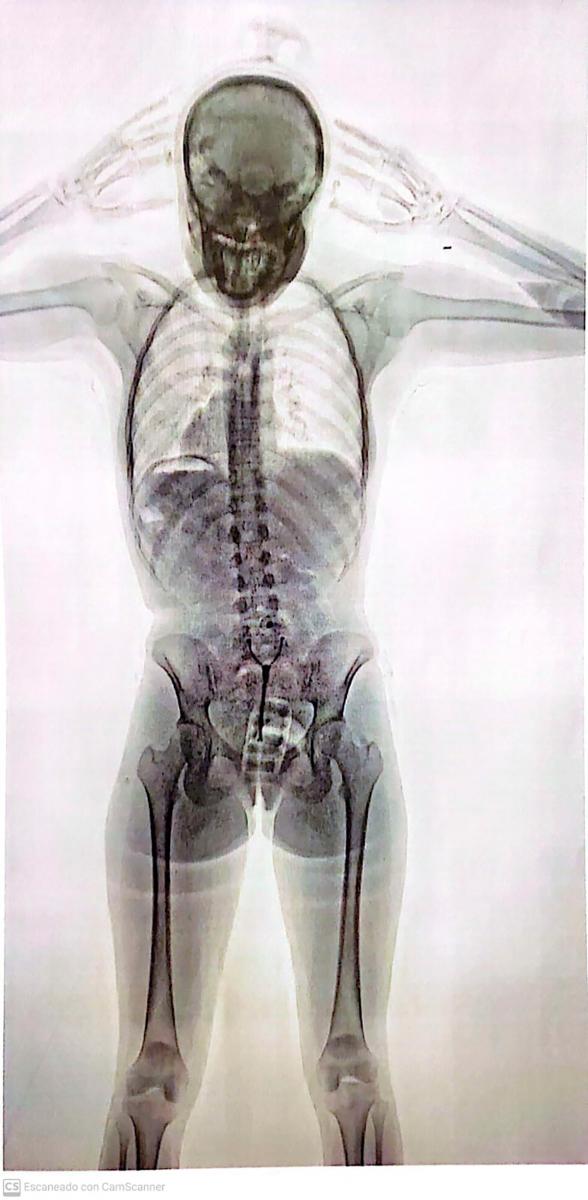

Planeaba abordar un vuelo con destino a Barcelona cuando fue interceptada por el personal de seguridad que la notó "nerviosa". Tras hacerla pasar por el Escaner de Rayos X detectaron los bultos dentro de su cuerpo y fue trasladada al hospital local para le sean extraidos.

En ese momento, la chica, que días antes había cumplido 20 años, respondió de manera «dubitativa e incongruente», por lo que los investigadores decidieron que pase por el Escaner de Rayos X.

Allí se descubrió que la joven había ingerido 78 cápsulas de 10 gramos de cocaína cada una y las llevaba dentro de su cuerpo, por lo que de inmediato quedó en calidad de detenida y fue trasladada al Hospital Zonal General de Agudos Doctor Alberto Antranik Eurnekian, donde quedó internada.

Una fuente judicial explicó a Télam que en el centro asistencial, «los médicos detectaron la presencia de elementos extraños introducidos en la zona vaginal y en el sistema digestivo», por lo que fue sometida a un tratamiento para la evacuación total de todas las cápsulas.